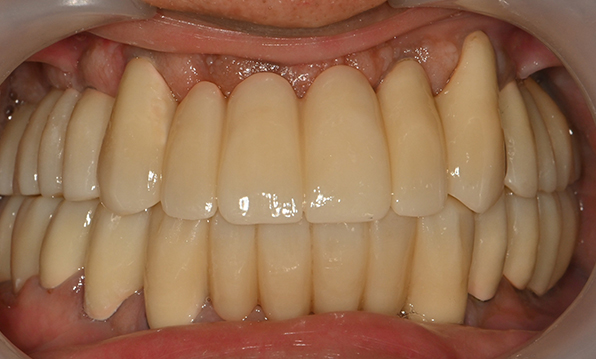

전체 임플란트

위 아래 치아가 정확하게 맞아야하는 고난이도 임플란트

임상 경험이 많은 숙련된 전문의의 섬세한 기술력이 중요합니다.

치아가 하나도 남아있지 않거나 전체적으로 상실된 경우 추천합니다.

치료기간 : 2021.04.12~2021.09.15